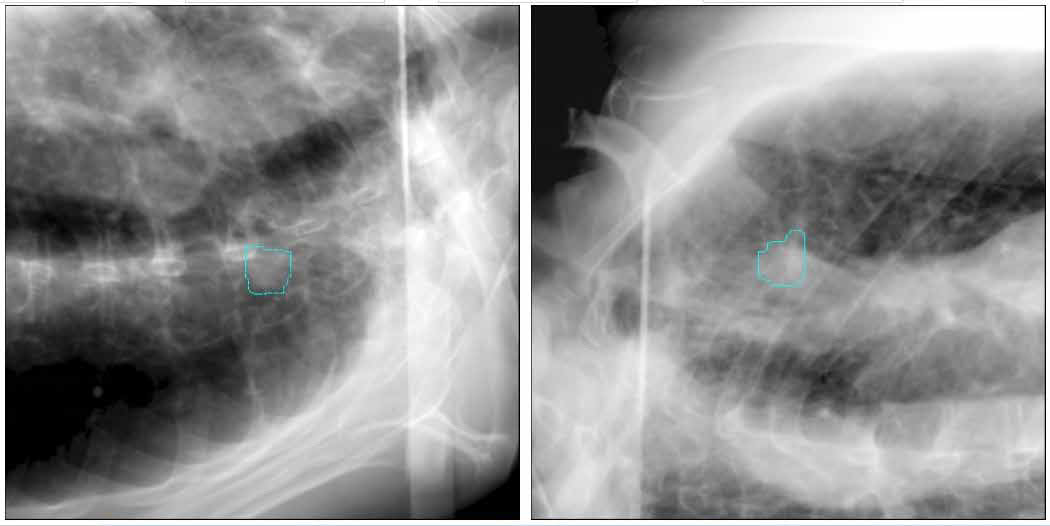

The cyberknife system enables safe and effective sbrt for central lung tumors surrounded by sensitive structures and lung tumors near the chest wall 3.

A faster return to everyday life. Reduced incidence of side effects the cyberknife system delivers the required radiation dose to the lung tumor with sub millimeter accuracy significantly reducing incidence of many of the most common side effects of lung radiotherapy such as shortness of breath. Potential side effects of cyberknife treatment for lung cancer. The cyberknife system is a leading technology in sbrt a specialized type of radiation therapy used to treat early stage inoperable non small cell lung cancer while minimizing side effects 1.

Sbrt or stereotactic body radiation therapy was adapted from central nervous system stereotactic radiosurgery a treatment technique that has been used to treat tumors of the brain and central nervous system for over 30 years. Possible side effects could include but are not limited to.

Lung Sbrt With Cyberknife Accuray